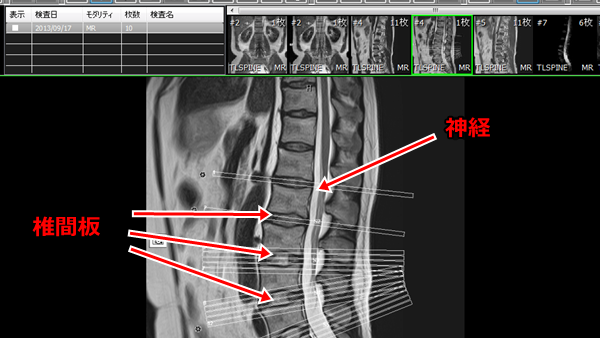

ほぼ3週間後、やっとMRI検査となる

結論から言うと、ヘルニアでは無かった。いわゆる椎間板ヘルニアは腰椎にある

椎間板が飛び出して神経に触れ、激しい痛みを生じ、歩行困難となるのだが

私の神経部には何も触れていなかった